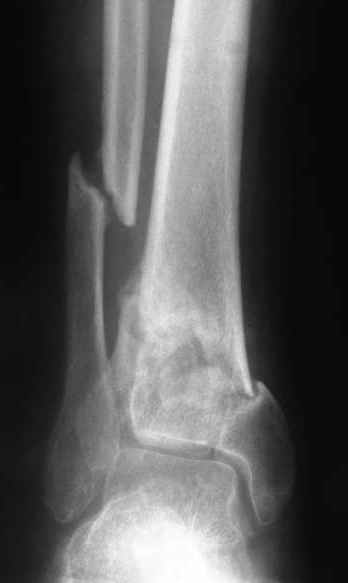

A 56 year old laborer fell off a wall approximately 5 months ago. He sustained an open pilon fracture. He was treated with debridement and external fixation. After he was treated for 4 months, the external fixator was removed.

The patient had no medical insurance and was therefore transferred to my care by his treating surgeon. He has remained NWB. He denies pain in his ankle. He has painless dorsiflexion and plantarflexion of his ankle joint.

I have attached his x-rays. I have also attached an WMV movie file of his axial CT (if you are unable to view this, I can post an MPEG file).

Suggestions for treatment?